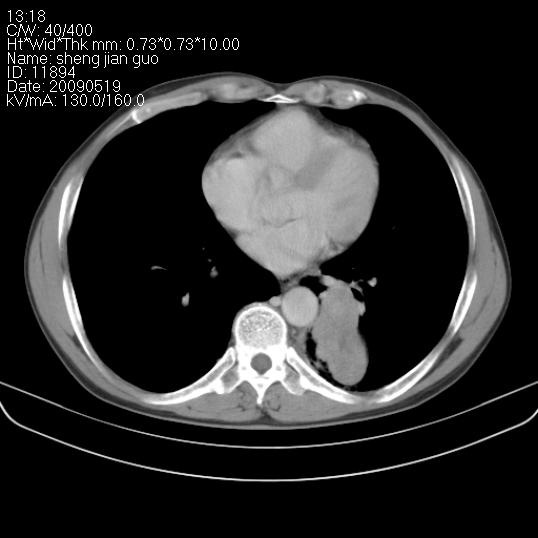

以下是引用zjzjr在2009-5-19 17:25:00的发言:[br]支持楼主考虑,另左肺下叶阻塞性炎症。

以下是引用zhao_bin2008在2009-5-19 17:48:00的发言:[br]支持左肺下叶周围型肺癌并阻塞性肺炎。

以下是引用zsl6918在2009-5-20 7:10:00的发言:[br]左侧中心型肺癌!